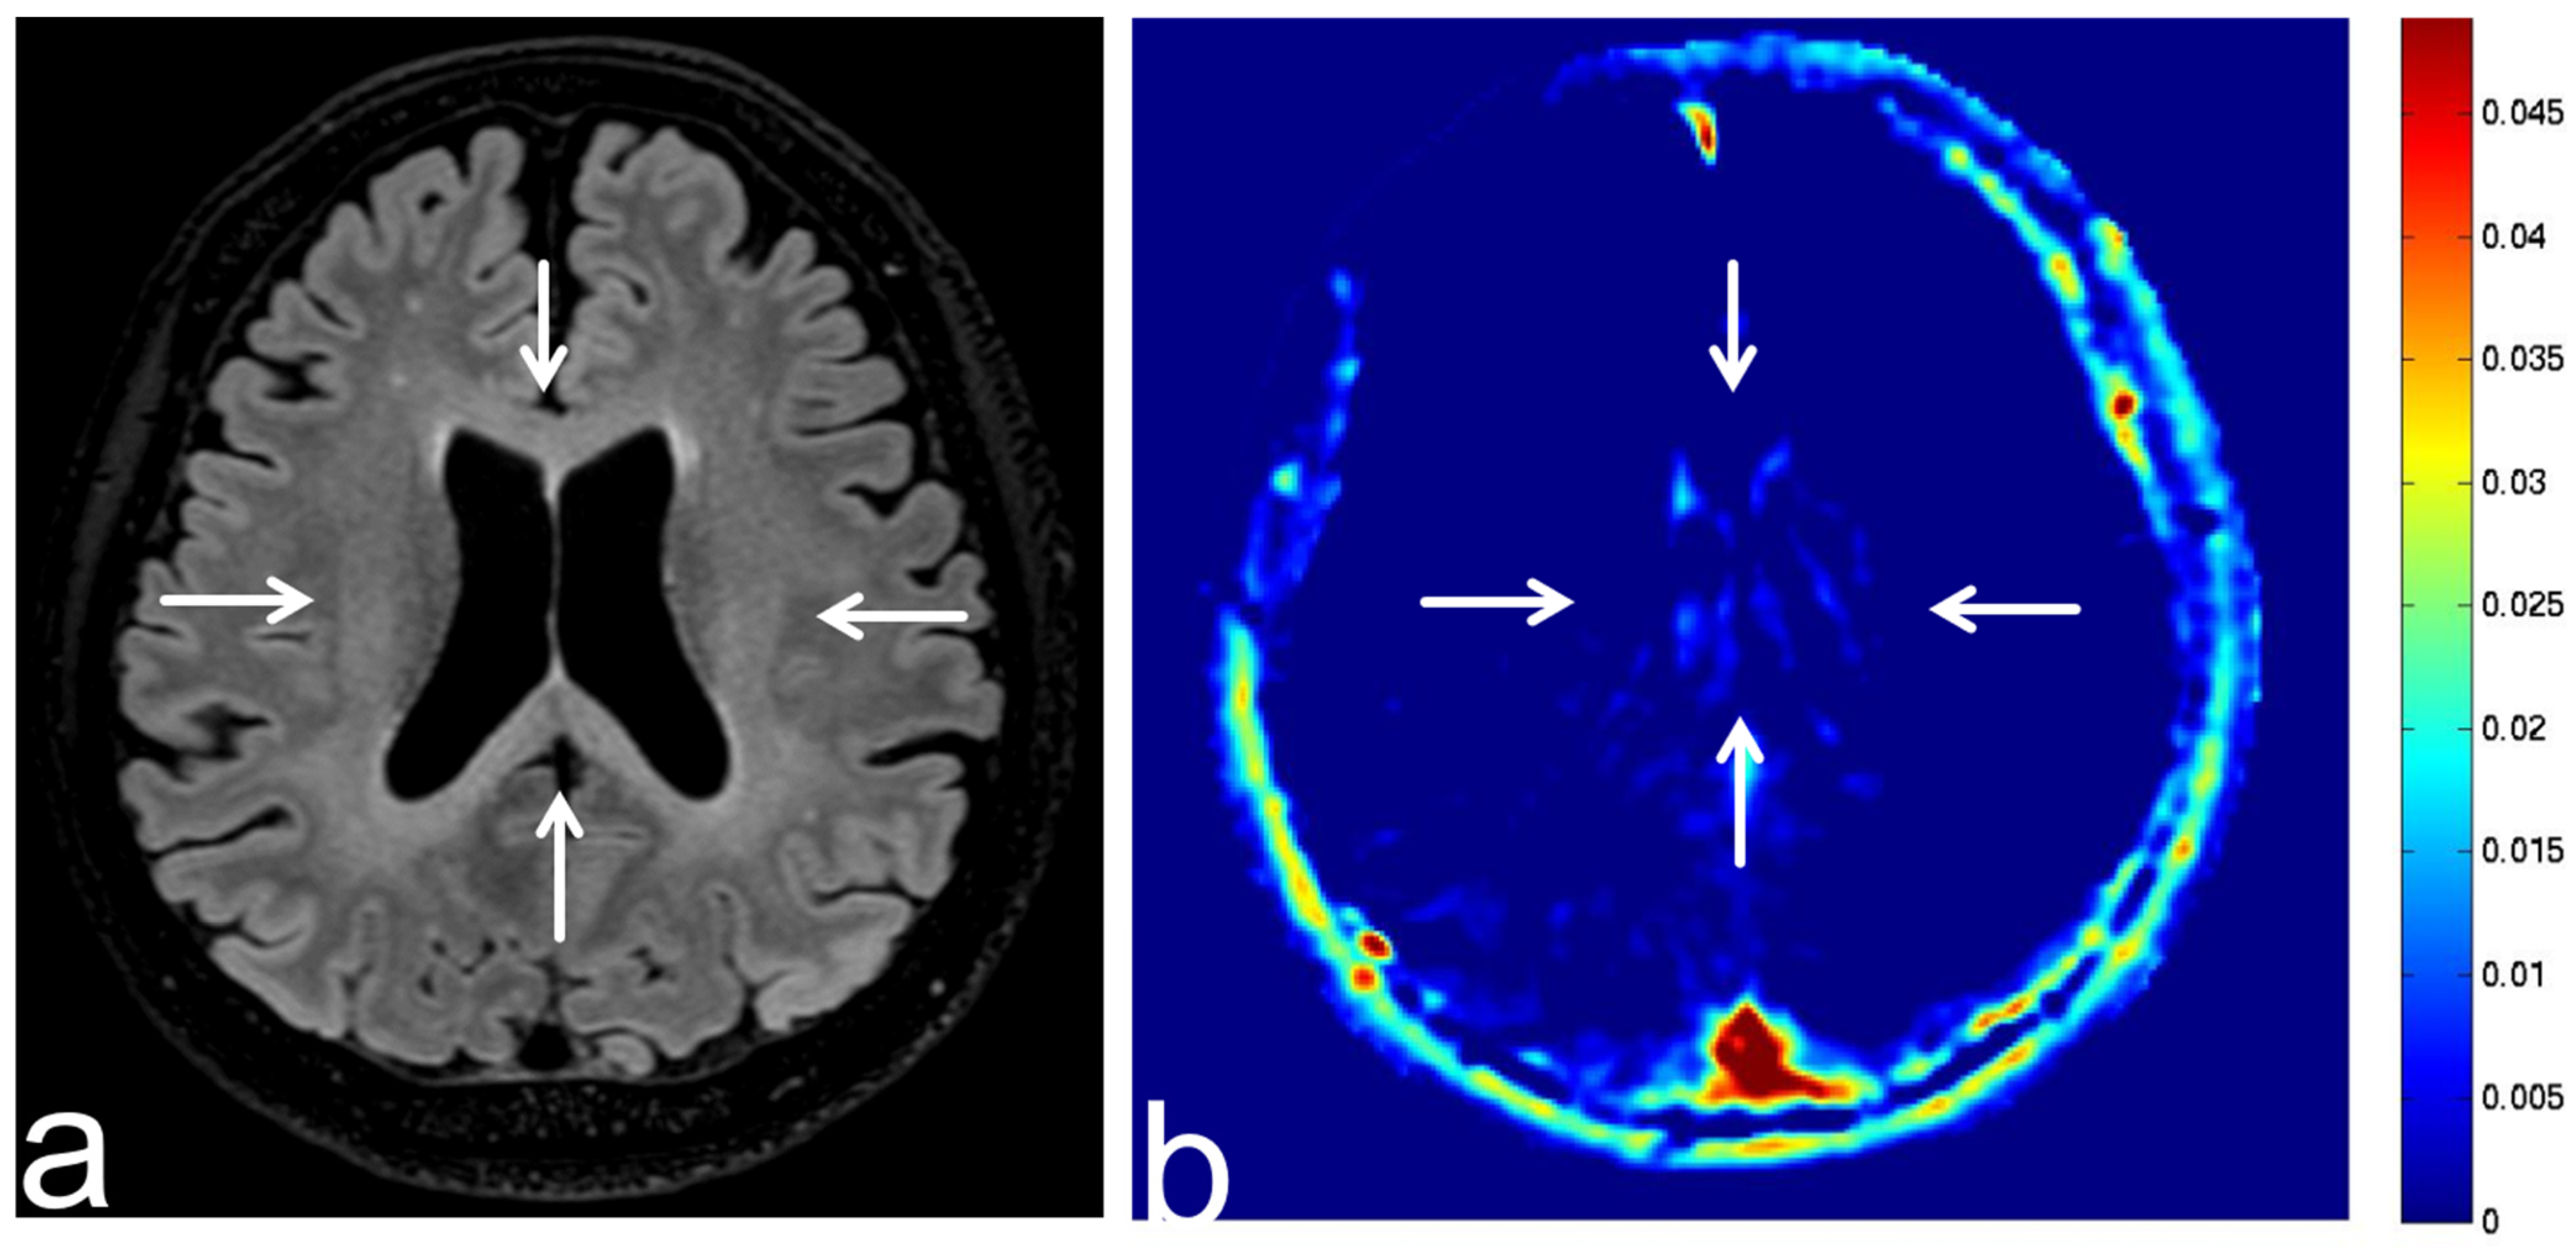

8.3. Tuberous Sclerosis Complex